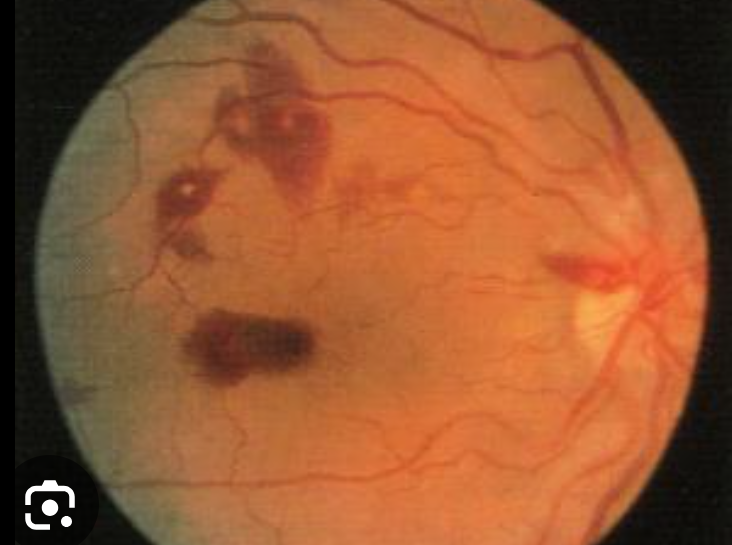

Q

What are Roth spots?

A

hemorrhagic retinal lesions with a pale centre seen on fundoscopy